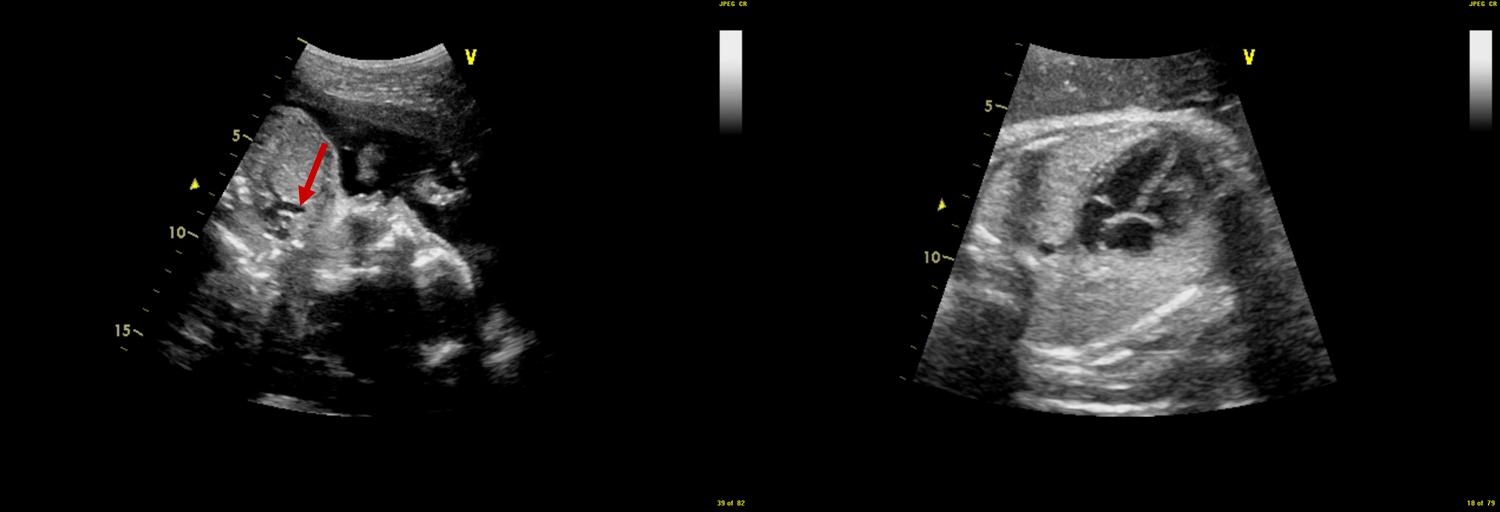

در 20 هفتگی، قلب به اندازه تصویر بند انگشتی شماست و قبل از تولد باید رشد زیادی انجام دهد. بنابراین، جای تعجب نیست که برخی از مشکلات قلب جنین در اسکن روتین هفته 18-20 مشهود نباشد. در شرایط بهینه تصویربرداری، می توان به بسیاری از ناهنجاری های اصلی مشکوک شد.

سونوگرافی قلب جنین به تخصص و تجربه زیادی نیاز دارد. غربالگری عمومی قلب به طور معمول در اسکن هفته 18-20 انجام می شود. اگر سوالی در مورد ناهنجاری قلب جنین وجود دارد، ارجاع فوری برای اسکن سوم ضروری است. در اسکن سوم، متخصص سونوگرافی جنین نه تنها قلب جنین را دوباره ارزیابی می کند، بلکه بقیه جنین را نیز از نزدیک بررسی می کند و به دنبال مشکلات احتمالی دیگر می گردد. در برخی شرایط، کاریوتایپ جنین (آزمایش کروموزوم‌های جنین) نشان داده می‌شود و به زوج CVS یا آمنیوسنتز پیشنهاد می‌شود.

برخی از ناهنجاری های قلبی حتی با معاینه دقیق متخصص در دوران بارداری قابل تشخیص نیستند. اینها معمولاً نقص‌های جزئی هستند، مانند سوراخ‌های کوچک در قلب، یا ناهنجاری‌های خفیف دریچه. علاوه بر این، برخی از نقایص قلبی تا پس از تولد آشکار نمی شوند. نتایج به شدت به وضوح قلب بستگی دارد و به موقعیت جنین و کیفیت تصویر مادر بستگی دارد.